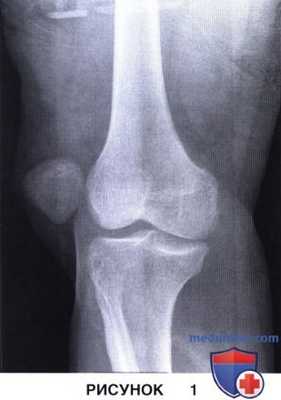

б) Стандартное рентгенологическое обследование включает рентгенограммы обоих коленных суставов стоя в прямой проекции, в боковой проекции при сгибании до 30°, в туннельной проекции и аксиальной («восход надколенника») проекции при сгибании до 30° и 45°, однако последние при свежей травме сделать бывает непросто. На рис. 1 представлена рентгенограмма в прямой проекции при вывихе надколенника:

• В области латерального канала или передней части вырезки нередко можно увидеть свободные фрагменты